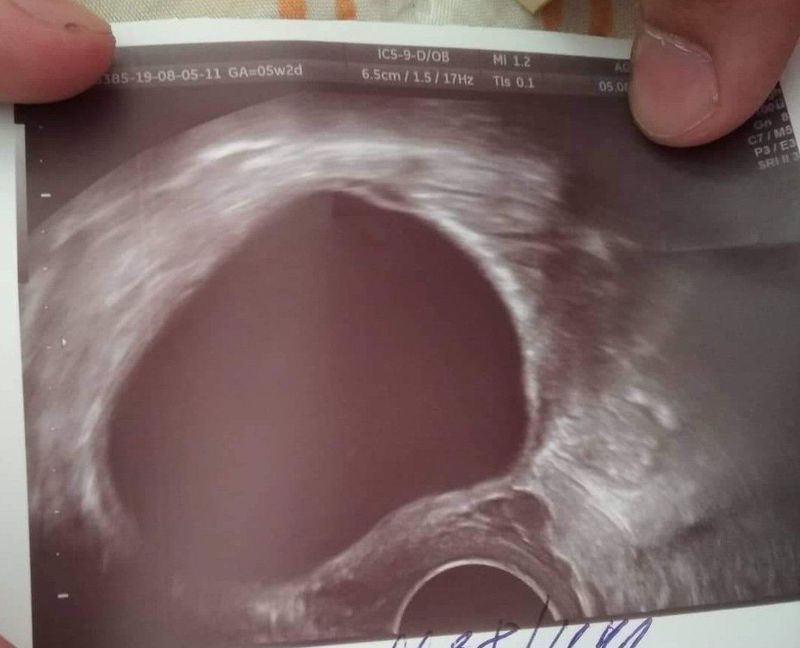

What is this

Yeah I know its vaginal ultrasound. I just wasnt sure if it was a cyst

Yeah it is cyst

It is vaginal ultrasound and it is syst